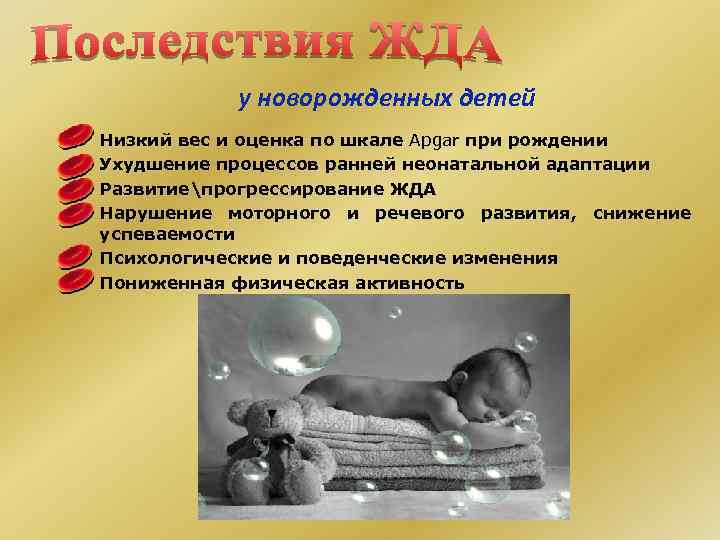

Шкала Апгар: что считать нормой для новорожденных